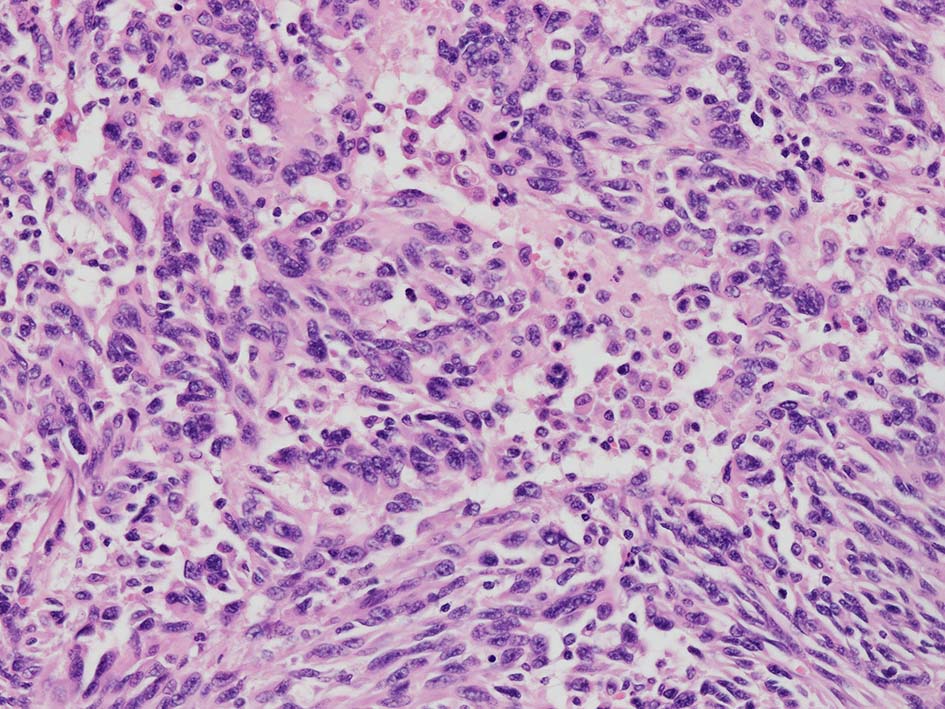

紡錘形異型メラノサイトが著明な間質反応(desmoplasia)を伴い増殖する特殊な色素性病変。*1. desmoplastic neurotropic melanomaは, desmoplastic melanomaのうち神経向性(neurotropism:神経周囲侵襲像)がめだつものでReedら*2が最初に報告した。

いずれも腫瘍細胞の異型性が乏しく, 背景の間質反応がめだつこと, メラニンの存在が目立たないことが特徴である。

病理組織所見*4

再発腫瘤病変の組織像